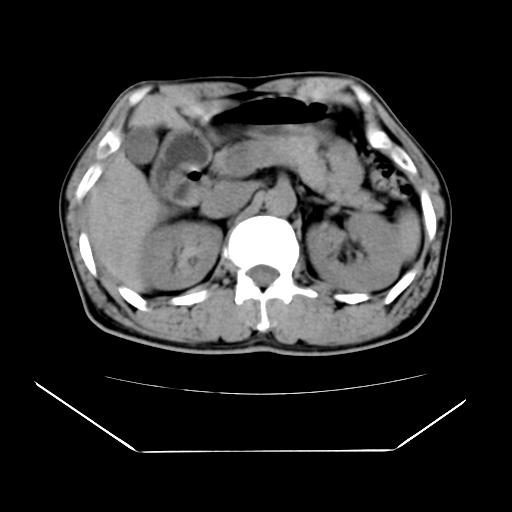

男性,55岁,外院体检afp明显升高,但b超未发现异常,否认乙肝病史。来我院ct增强。有延时扫描。

肝脏右叶动脉期可见低密度影,至延迟期被充填,考虑血管瘤可能性大。

肝右叶病灶

不排除肝右叶肝癌可能。

这个不是肝右静脉吗,这么大的病灶b超不可能发现不了吧

如果这个是癌灶的话则下腔静脉有瘤栓可能

肝6段血管瘤

血管瘤可能性大。

是肝右静脉吧

考虑肝右静脉影。